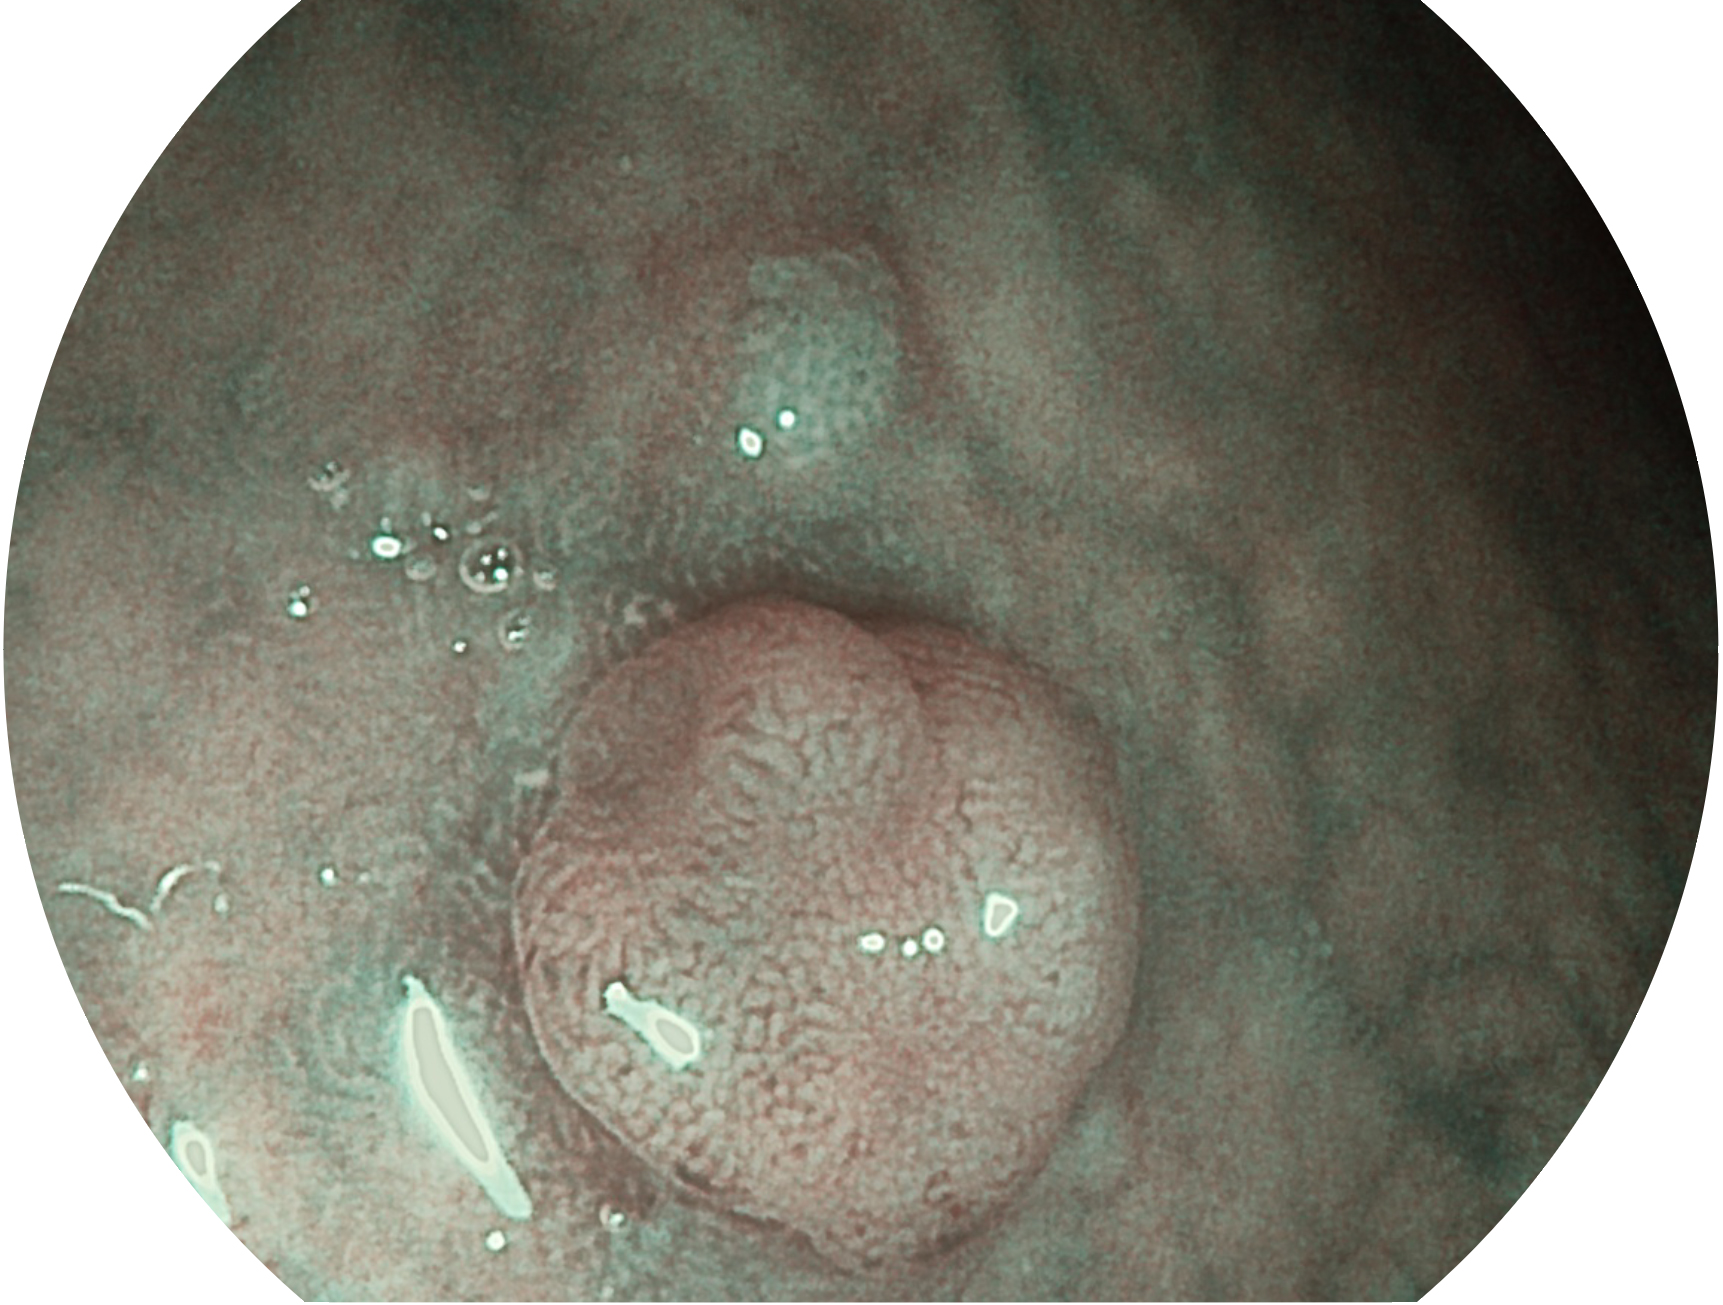

与上一代VIST相比,摒弃了滤光转轮而直接采用光谱组合的方案,加入了血红蛋白吸收高峰与次高峰的蓝紫光和绿光光谱,更有利于黏膜血管吸收,突显浅表层血管和中层血管的对比度,因而具备更高的图像对比度,近景观察时,有助于微细结构变化及病灶边界的观察。

• 白光图像 VIST图像